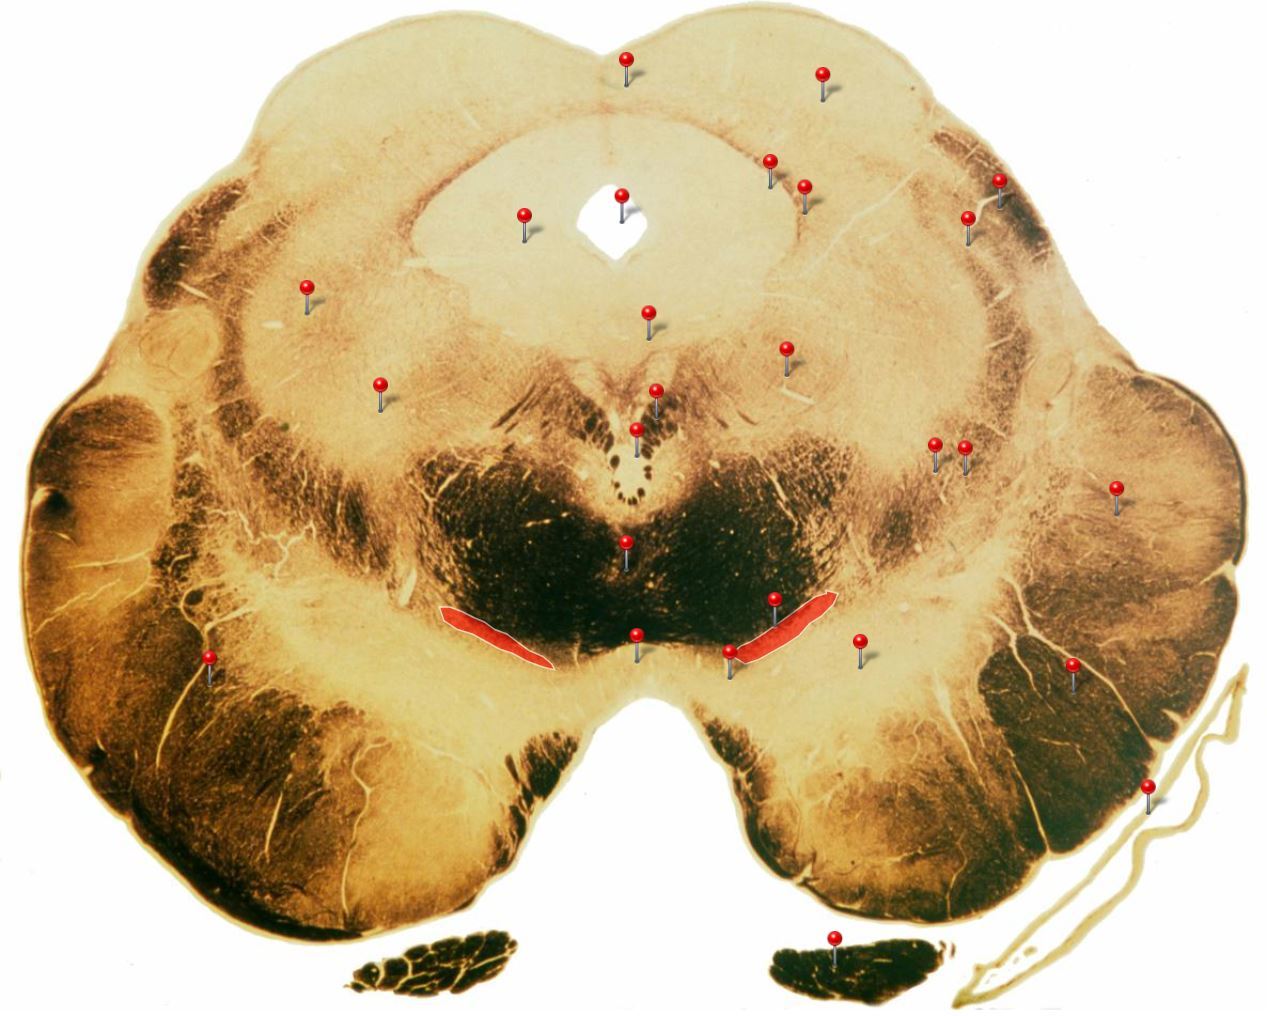

Corticospinal Tract

Rostral Medulla

Controls precision and speed of skilled movements involving the distal muscles of the contralateral limbs, particularly those of the hands and fingers

Nucleus Ambiguus

Neurons supply the muscles of the pharynx, larynx, upper oesophagus and heart

Basilar Artery

Provides blood supply to much of the cerebellum, pons, midbrain and posterior thalamus as well as part of the temporal (inferior surface) and occipital (medial and inferior surfaces) lobes

Olives

Elevations formed by the inferior olivary nuclei which integrate information from a variety of sources before relaying it to the cerebellum

Rubrospinal Tract

Assists in the control of movements of the hands and fingers

Medial Vestibular Nucleus

Process inputs from vestibular receptors of the inner ear and are involved in the regulation of posture and the coordination of head and eye movements

Spinal Trigeminal Tract

Transmits somatosensory (crude touch, pain and temperature) inputs from the Trigeminal nerve (CN V) through the midpons and medulla to the spinal trigeminal nucleus.

Ventral Cochlear Nuclei

One of the relay nuclei for the auditory fibres of the vestibulocochlear nerve (CN VIII) and functions to modify inputs to the higher auditory structures

Medial Longitudinal Fasciculus

Pathway through which eye movements are coordinated with changes in head position

Dorsal Cochlear Nuclei

One of the relay nuclei for auditory fibres of the vestibulocochlear nerve (CN VIII) and functions to modify inputs to the higher auditory structures

Inferior Olivary Nucleus

Plays an important role in the learning of new motor skills

Solitary Nucleus

Processes visceral afferent (GVA and SVA [taste]) inputs from CN VII, IX and X and relays them to the reticular formation and visceral efferent nuclei

Spinal Trigeminal Nuclei

Processes sensory inputs, particularly pain and temperature, from the head and neck and relays them to the ventral posteromedial nucleus of the thalamus

Inferior Vestibular Nucleus

Plays a role in the maintenance of balance and the coordination of eye and head movements

Medial Lemniscus Rostral Medulla Transmits sensations of **discriminative touch, vibration, proprioception** an **stereognosis** from the *gracile* and *cuneate nuclei* to the *ventral posterior nuclei of the thalamus*

Ventral Spinocerebellar Tract Rostral Medulla Provides feedback to the cerebellum concerning motor activity (including reflexes) in the lumbosacral levels of the spinal cord

Glossopharyngeal Nerve (CN IX) Rostral Medulla Transmits taste and tactile sensation from the posterior part of the tongue, pharynx and ear, and visceral sensation from the chemo- and baroreceptors of the carotid body and sinus (also supplies efferent fibres to the otic ganglion and stylopharyngeus m.)

Inferior Cerebellar Peduncle Rostral Medulla Formed by pathways passing in both directions between the medulla and cerebellum

Tectospinal Tract Rostral Medulla Function in humans not precisely determined; thought to mediate reflex movements of head in response to visual and perhaps auditory stimuli

Olivocerebellar Tract Rostral Medulla Transmits information from inferior olivary nucleus to the *contralateral* cerebellum, where it forms the **climbing fibres**

Lateral Vestibular Nucleus Rostral Medulla Contains cell bodies of the (lateral) vestibulospinal tract which regulates the activity of **axial** and **proximal** limb muscles in order to **maintain balance and posture**